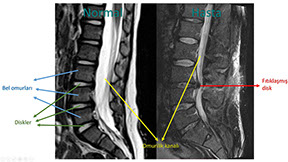

Tanıda manyetik rezonans incelemesi önemli bir yer tutar.

Yukardaki şekilde normal (solda) ile bel fıtığı olan bir hastanın (sağda) omurgalarının manyetik rezonans incelemeleri karşılaştırılmıştır. Filmleri incelerken yandan baktığımızı aklınızda tutun. Buna göre sağ taraftaki hastanın 3. ve 4. bel omurları arasındaki diskin bir parçasının yerinden çıkarak omurilik kanalına doğru yer değiştirdiğini ve bu bölgedeki sinirlere baskı yaptığını görebilirsiniz.